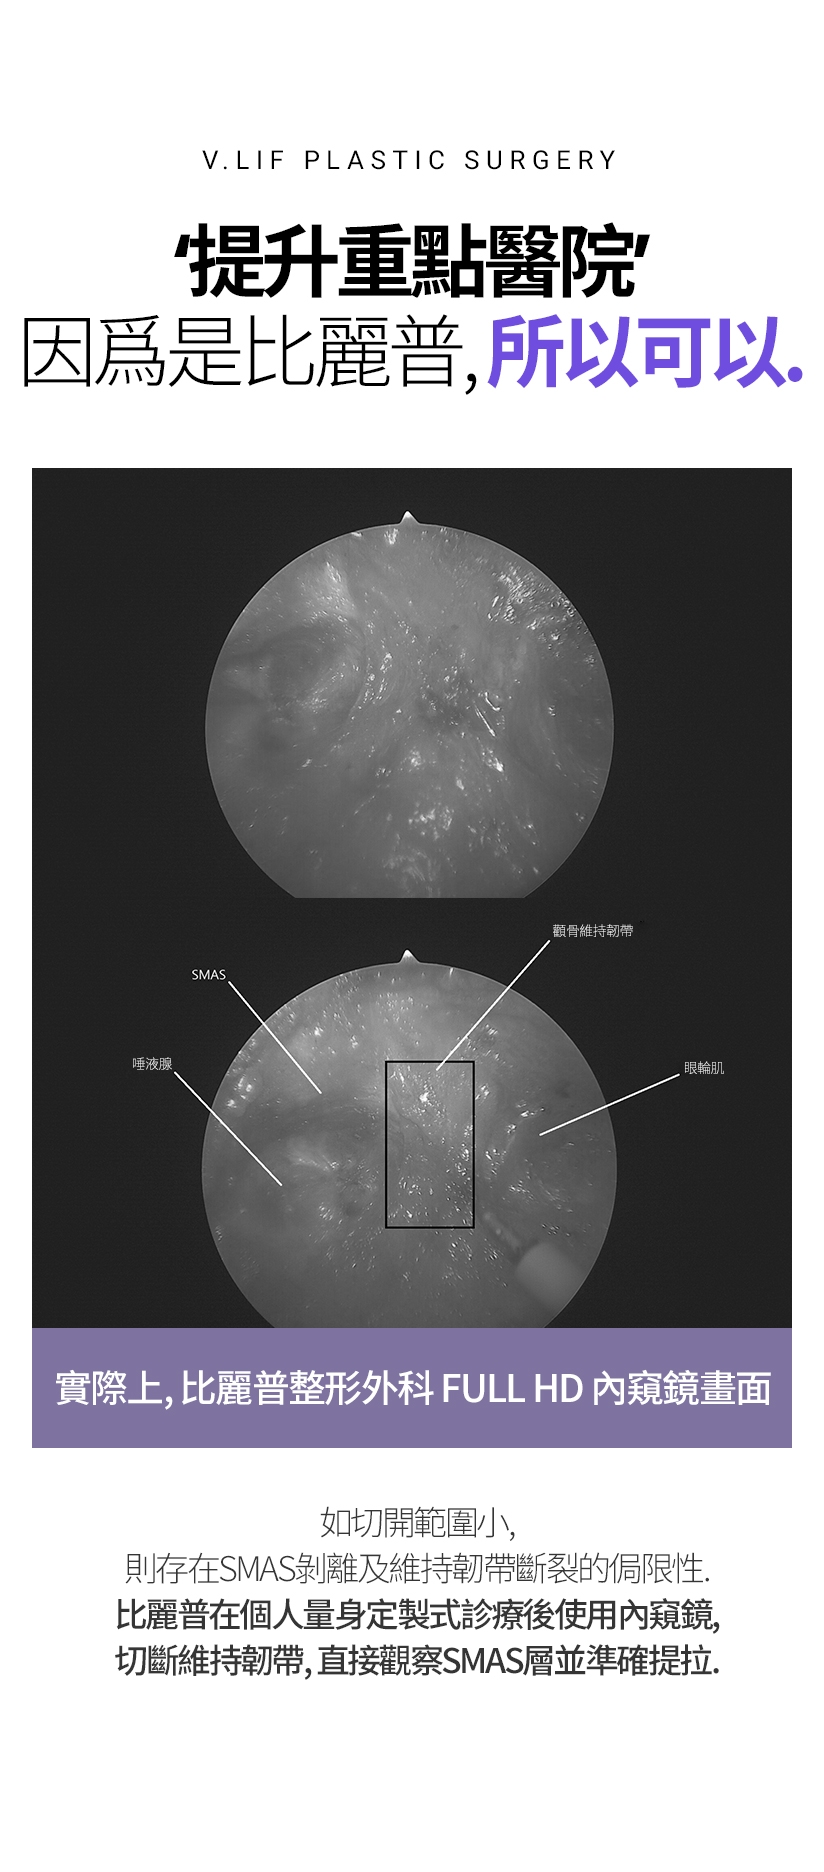

提升重點醫院 因爲是比麗普,所以可以。實際上,比麗普整形外科 FULL HD 內窺鏡畫面 如切開範圍小,則存在SMAS剝離及維持韌帶斷裂的侷限性。 比麗普在個人量身定製式診療後使用內窺鏡,切斷維持韌帶,直接觀察SMAS層並準確提拉。